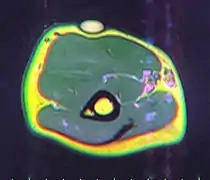

A physical exam is typically the easiest way to diagnose it. Rarely, a tissue biopsy or imaging may be required. The imaging modality of choice is magnetic resonance imaging (MRI) because it has superior sensitivity of distinguishing it from liposarcoma as well as mapping the surrounding anatomy.[22]

MRI showing lipoma of the arm